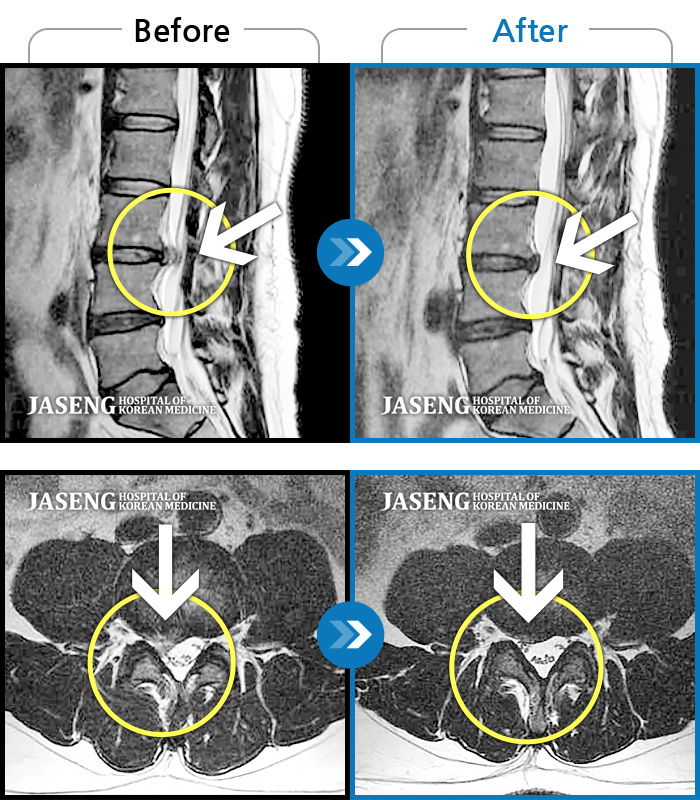

허리디스크

잠실 · 한상욱 원장

허리, 우측 엉치와 다리 후면 및 발끝까지 저림과 통증이 심하고 힘까지 빠진다.

촬영시기

2022.06.15 ~ 2022.11.11

2022.12.02

조회수 487